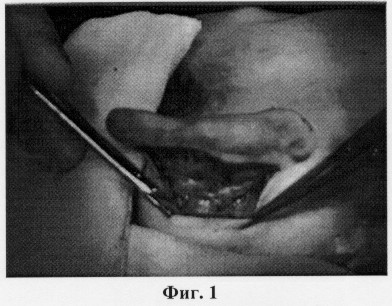

Операцию по коррекции формы ушных раковин выполняют под местной инфильтрационной анестезией. Проводят анестезию задней поверхности ушной раковины и области сосцевидного отростка. Затем на задней поверхности ушной раковины выполняют кожный разрез по краю завитка. Проводят тщательный гемостаз. Кожу по задней поверхности ушной раковины отслаивают до середины кривизны завитка, в нижней части от заушной мышцы и сосцевидного отростка приблизительно на 1 см, освобождая хрящ и выделяя заушную мышцу, что представлено на фиг.1. После этого иссекают заушную мышцу (фиг.2). После иссечения заушной мышцы выполняют наложение конхососцевидного шва, в который захватывают надкостницу сосцевидного отростка и хрящ ушной раковины (фиг.3), приближая ушную раковину к поверхности головы на необходимое расстояние. При этом хрящ прошивают на всю его толщину, нить проходит под кожей передней поверхности ушной раковины (фиг.4). Затем формируют противозавиток, накладывая сначала шов в области ножек противозавитка, затем в верхней его части, предотвращая нарушение контура противозавитка. Если хрящ имеет значительную упругость, то дополнительно накладывают 1-2 шва в средней части противозавитка (фиг.5). На фиг.6 представлен вид ушной раковины после наложения кожного шва.